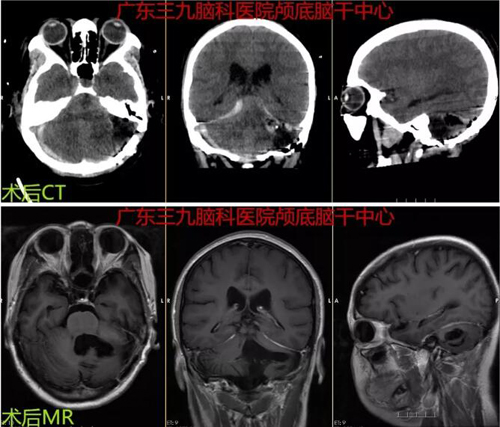

图3:术后CT及 MR示左侧小脑占位性病变切除术术后改变